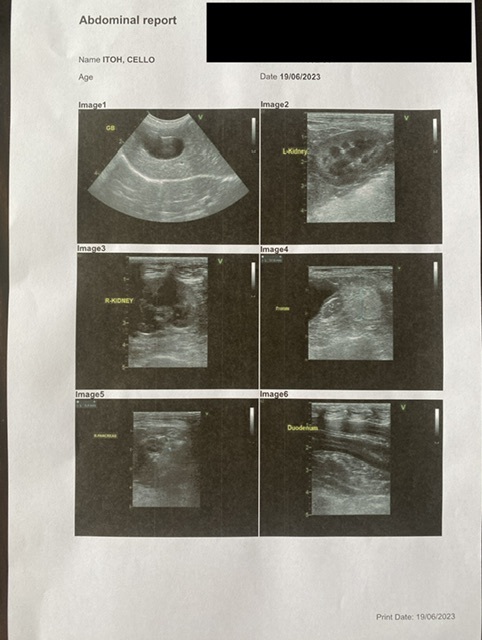

↑腹部の超音波

手術をするにあたり、リスクとなる他の持病がないかを調べてもらいました。

結果は持病なしでした。